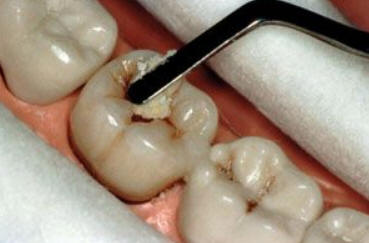

Sólo se lleva a cabo en  cavidades pequeñas ( que involucra solo la dentina ) y en aquéllas que son accesibles para los instrumentos de mano. Con el instrumental de mano se elimina la dentina desorganizada e infectada hasta llegar a la dentina desmineralizada. Ver figura inferior.

Técnica TRA:

El tratamiento  restaurativo atraumático (TRA) o Atraumatic Restorative Treatment (ART) incluye prevención, eliminación de caries por medio de instrumental de mano y la obturación con material adhesivo (ionómero vítreo). Esta técnica es simple y de bajo costo, en comparación con el método convencional que necesita para su efecto instrumental rotatorio y equipamiento eléctrico. El TRA es posible realizarlo en áreas rurales, escuelas, centros de salud con equipamiento mínimo. Solo hace falta improvisar una camilla para el paciente y un  taburete para el operador; los instrumentos necesarios y materiales para el TRA puede llevarse fácilmente en un bolso pequeño. El TRA es un  tratamiento alternativo perfecto para  caries dental en  países en vías de desarrollo dónde es frecuente las exodoncias como único tratamiento para eliminar o reducir la infección dental.

Instrumental necesario para el TRA: Pinza para algodón, espejo bucal y explorador como instrumental de exploración y preparación del campo.

Cucharitas de Black o pequeños excavadores para eliminar tejido cariado. Hachuela y azadón para el tallado del ionómero vítreo.

Se aísla el campo operatorio con rollos de algodón. Se limpia la cavidad con una torunda de algodón embebida en agua y luego se seca con torunda. Se utiliza la hachuela para ampliar la cavidad de caries, luego se elimina la caries con  cucharitas o excavadores.

Preparar el ionómero vítreo como indican la instrucciones del fabricante. Obturar con ionómero la cavidad y las fisuras remanentes.

Frote el  índice enguantado con vaselina y el material del relleno se aprieta firmemente con el dedo en el diente. Espere unos minutos y comience el tallado del material con el azadón.

La obturación terminada debe abarcar todas las fosas y fisuras,.